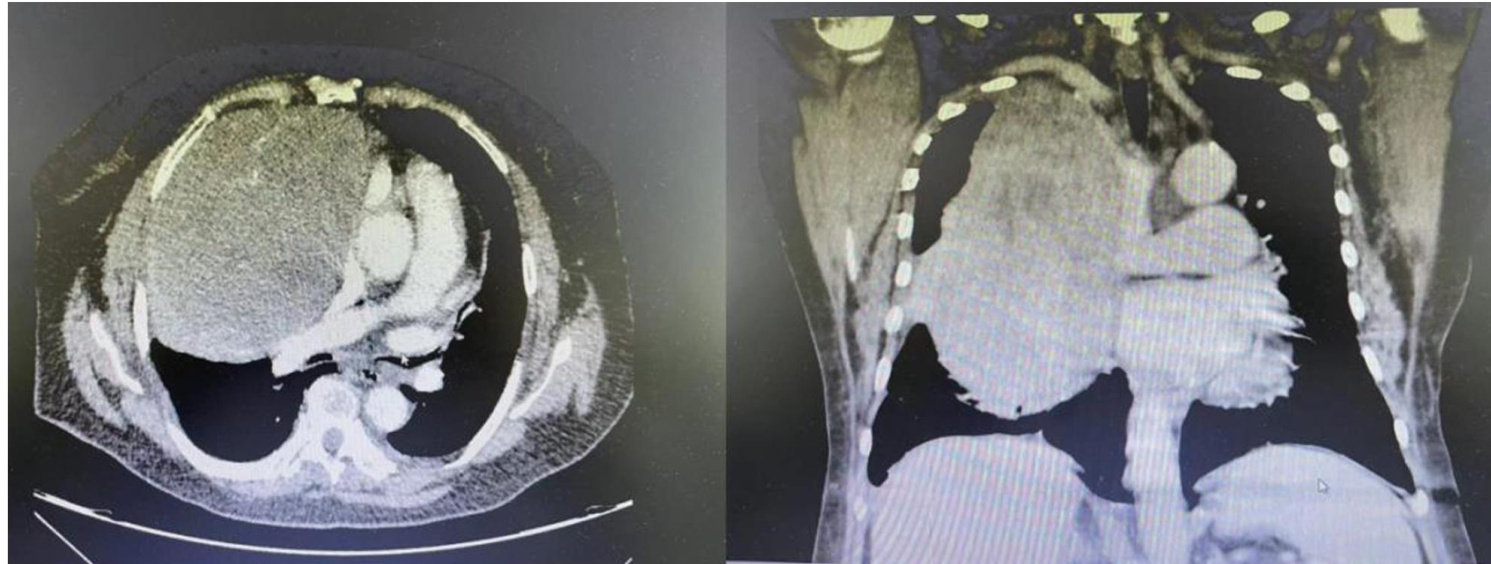

患者,女,78岁,近3月来反复胸闷、气促,伴双上肢及颜面部水肿。入院查体:颈部及颜面部水肿,颈静脉怒张,右侧胸廓相对饱满,右上肺呼吸音减低,双肺均未闻及明显干湿性啰音。胸部增强CT检查结果:右侧前纵隔可见类圆形包块,边界尚清,约 215mm× 155mm×124mm 大小,密度不均,右侧邻近肺组织受压,右侧支气管狭窄,右心房及上腔静脉受压,纵隔左移(图1)。(剩余3306字)